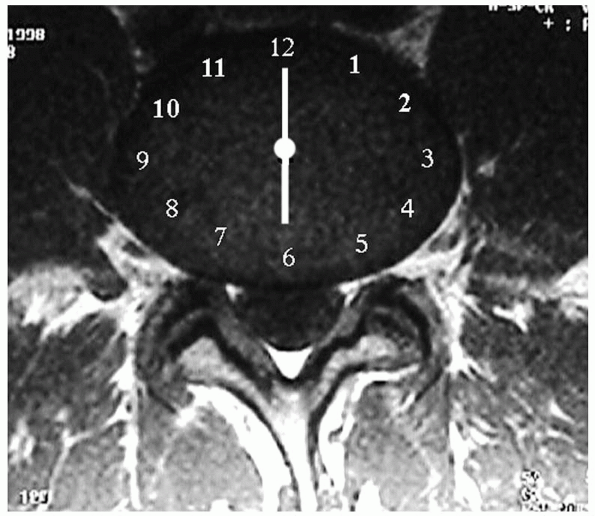

FIGURE 17-2.

Magnetic resonance imaging. 6-o’clock position, central disc; 5:30 or 6:30, posterolateral disc; 5-o’clock or 7-o’clock position, intraforaminal disc; 3:30 to 4:30, extraforaminal disc; 7:30 to 8:30, far-lateral disc. |

Herniations are central, posterolateral, intraforaminal, or

extraforaminal. Each type has a specific position on a clock face that

is visually “templated” over the cross-sectional view of a disc (Fig. 17-2).

The 12-o’clock position is the disc’s anterior midline; similarly, the

6-o’clock position is the posterior midline. The apex of a central

herniation occurs at the 6-o’clock position, and the apex of

posterolateral herniations are at the 5:30 (left) or 6:30 (right)

position, depending on if the herniation occurs on the left or right.

The apex of intraforaminal herniations are centered at the 5-o’clock or

7-o’clock position, and the apex of extraforaminal disc herniations are

positioned between 3:30 and 4:30 on the left or 7:30 and 8:30 on the

right. The latter type is also termed far-lateral herniations and is

notable for affecting the upper root. For example, a far-lateral L4-5

herniation affects the upper L4 root after it exits from under the L4

pedicle, rather than affecting the more medial L5 root (Figs. 17-3, 17-4 and 17-5).